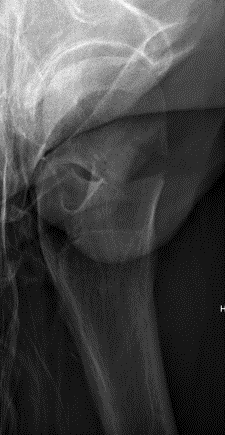

Closed versus open reduction

Union rates increased with anatomical reduction

- RCT of 92 patients with displaced subcapital fractures < 50 years

- randomized to open versus closed reduction

- no difference in union rates between groups

- increased nonunion with non anatomical reduction

Haidukewych et al JBJS Am 2004

- 51 displaced subcapital fractures < 50

- 10% incidence of nonunion

- 27% osteonecrosis

- nonunion 4% with good to excellent reduction

- nonunion 80% with poor reduction (>10 mm of displacement, >20°, any varus)